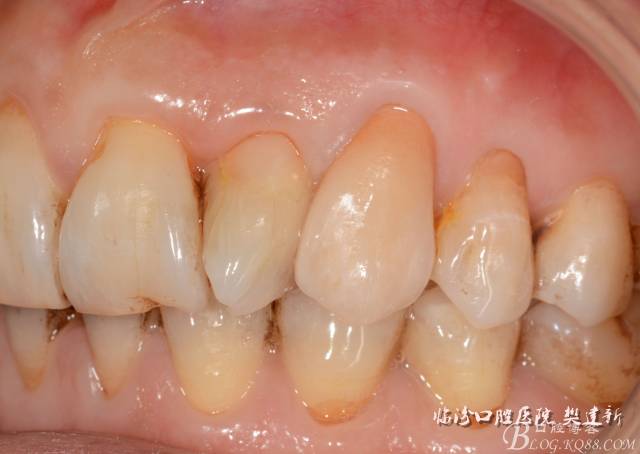

口內(nèi)檢查: 23殘根,位于齦上3MM,根管口探無反應(yīng),叩(+-),無松動,牙周無紅腫.X片示:23根管無阻射,根尖骨密度降低.11.12.13頸部楔形缺損,探敏感,牙髓活力正常.全口牙結(jié)石色素(+).

圖1 23口內(nèi)修復(fù)前情況:殘根位于齦上3MM,牙周無紅腫.